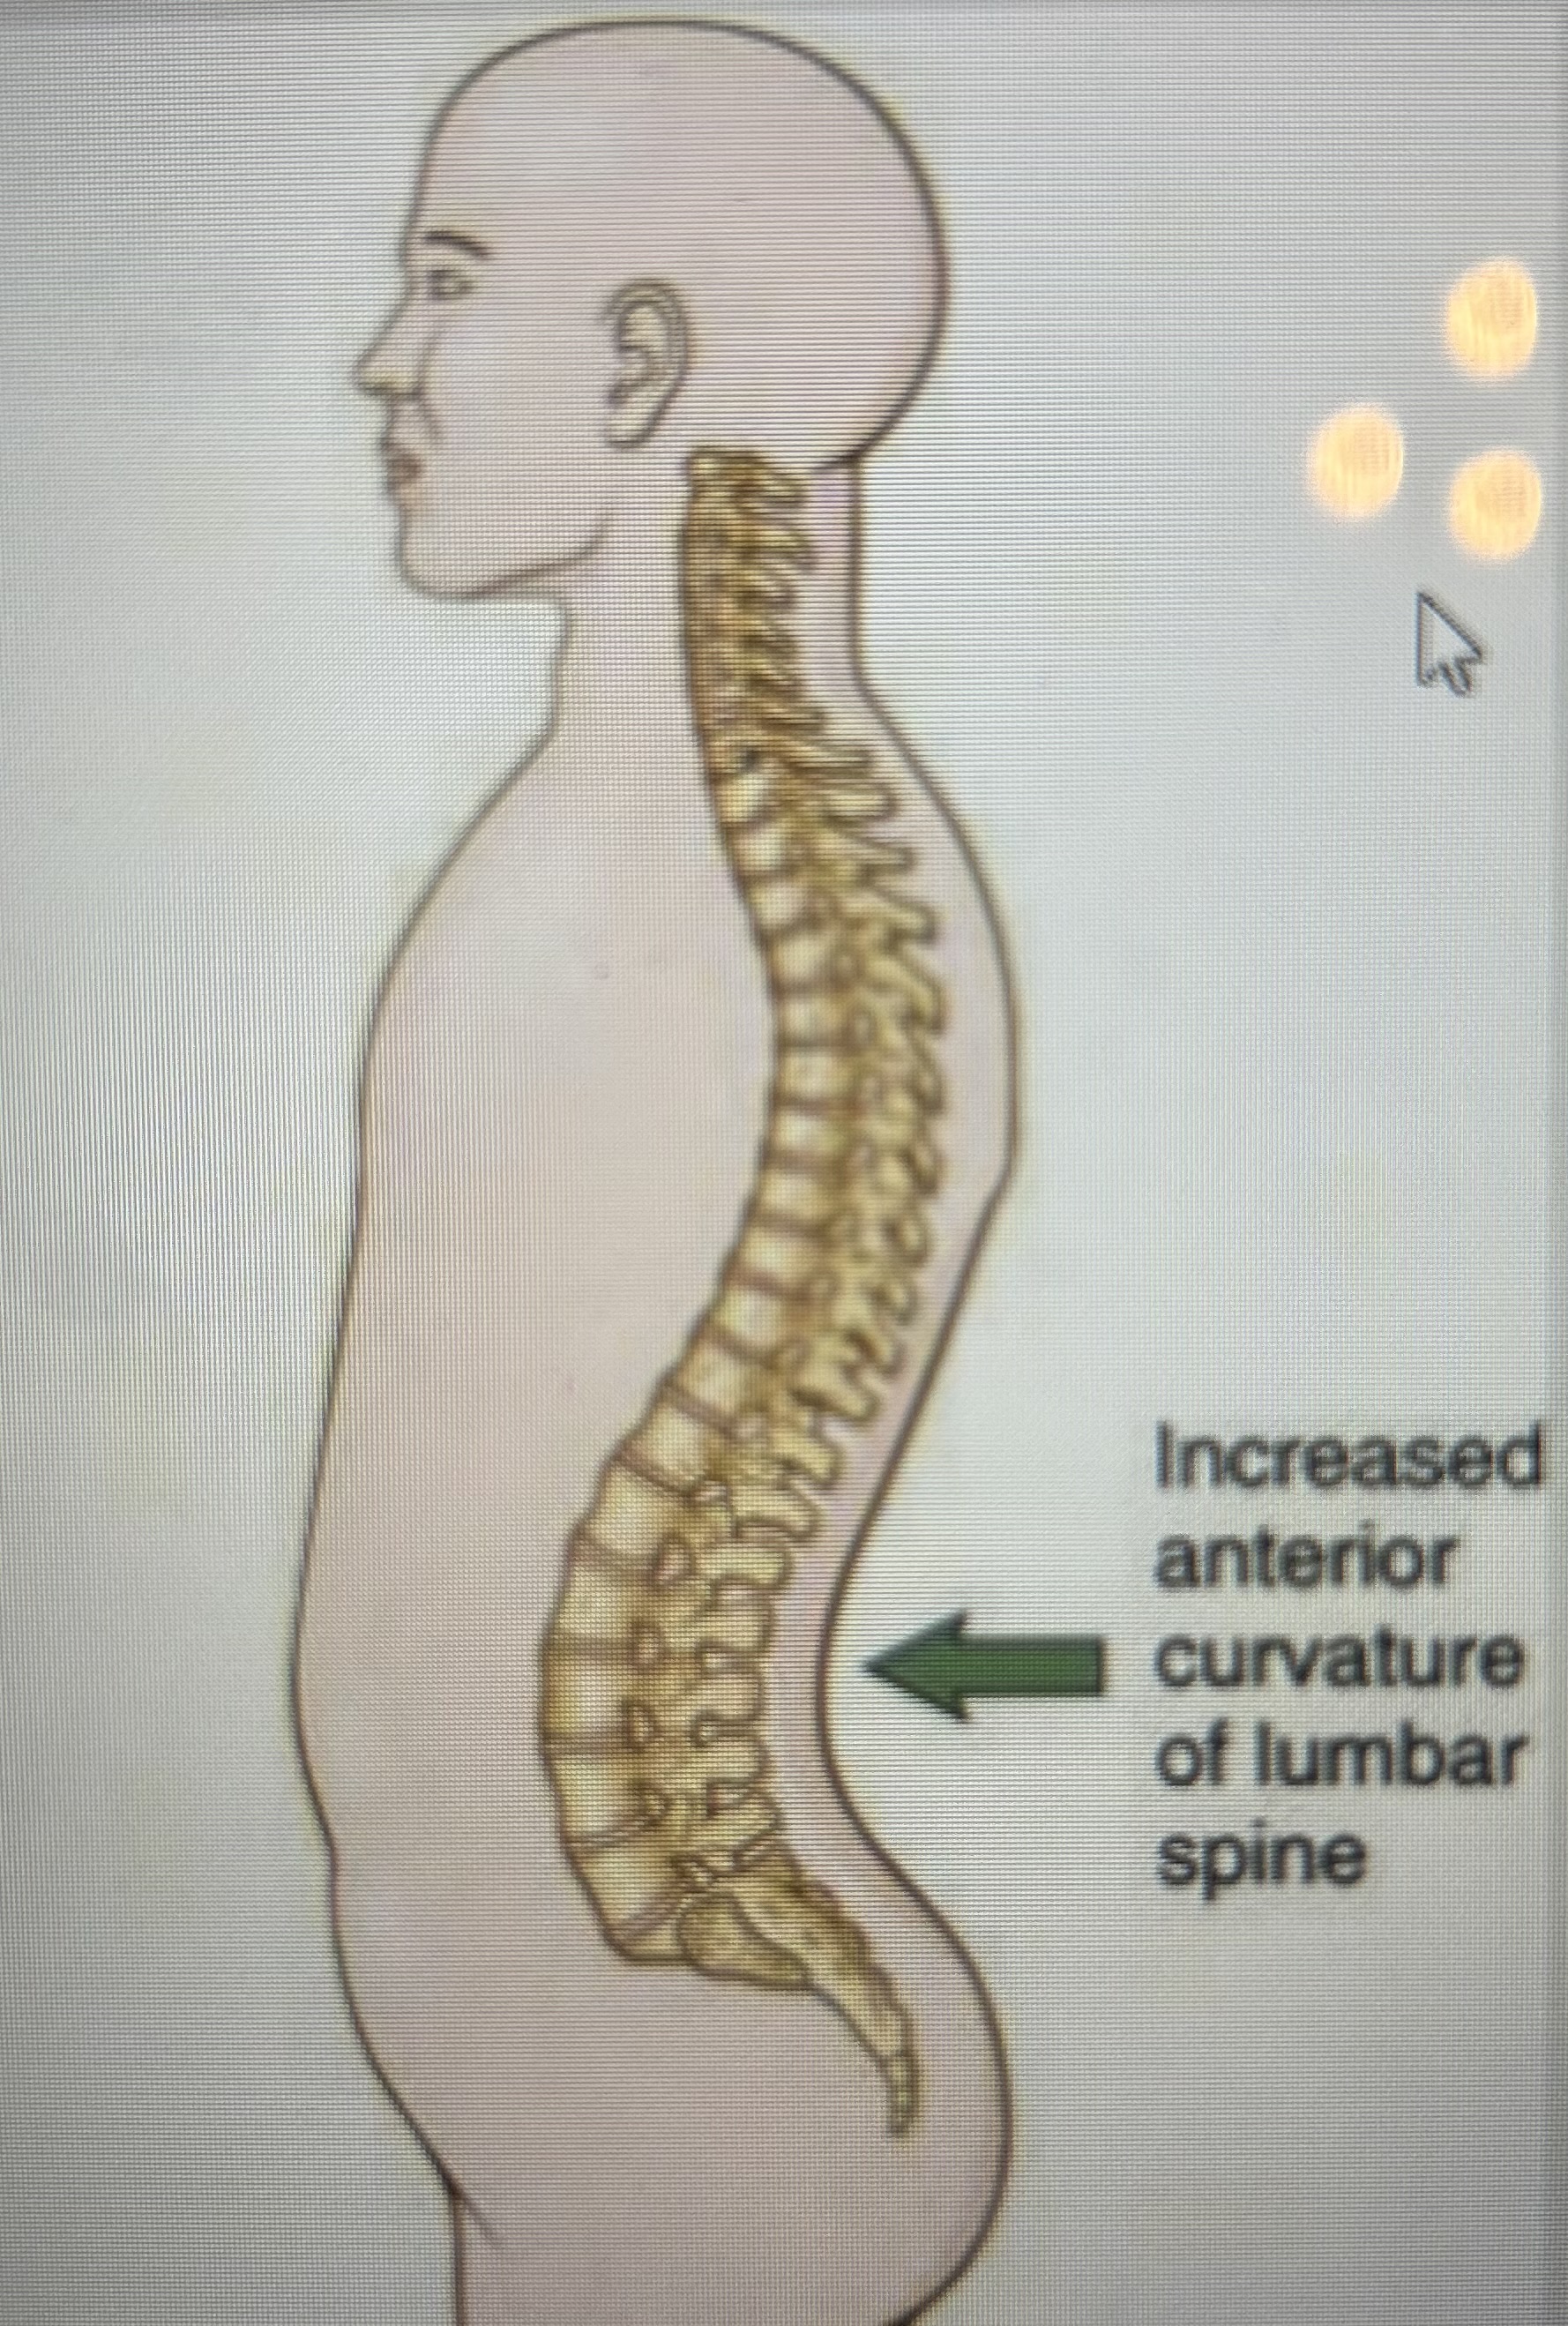

kyphosis

increased posterior curvature of the thoracic spine

lordosis

increased anterior curvature of lumbar spine

What is this spinal curvature?

Lordosis